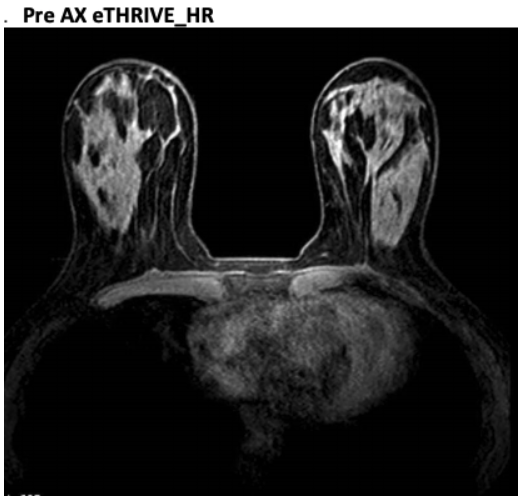

PRE AX eTHRIVE_HR THRIVE FOV to cover both breasts OK to add slices but each dynamic time must remain below 90 seconds. Make sure the shim volume is centered on the Sag view for both breasts. IF FAT SAT FAILS: Turn off Fat Sat and repeat. You must also turn off Fat Sat on the POST!! Refer to the below image to see an example of when fat sat fails. This sequence pictured would need to be repeated again without fat sat, and the post Thrive would also need to be run WITHOUT fat sat

MR Breast PRE AX eTHRIVE FS

MR Breast Pre AX eTHRIVE FS - example of failed FS